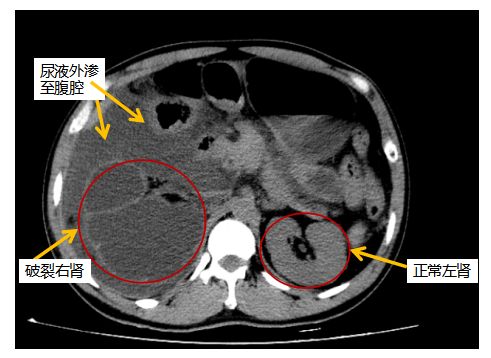

ct显示:右肾破裂,右肾周组织及腹腔脏器广泛粘连。

检查出“右肾结石”。由于经济条件不好,加上疼痛不明显,发作也不频繁,就没当回事。三年前,他来到深圳一家工厂打工,每天要坐8个小时以上,忙起来连喝水、上厕所也顾不上,腰痛情况有所加重。但总觉得是多年的老毛病,问题不大,加上还要挣钱养家,就继续听之任之。

当晚7时许,段燚星教授带领郭玺、郭琼等医护人员为吴胜施行手术。术中发现,腔静脉、胰腺、肝脏、升结肠严重粘连,还合并有腹腔积液、胸腔积液、肠梗阻,肾静脉与下腔静脉粘连严重处有裂口,手术难度非常大。手术团队争分夺秒,小心翼翼地将破裂的右侧肾脏和输尿管完整切除,清除肾周血肿约3000毫升,同时完成分解粘连、腔静脉修补等一系列高难度操作,手术耗时约3小时顺利完成。术后,吴胜生命体征平稳,家人感激得热泪盈眶,同时也十分懊悔,“没想到结石会有这么严重的后果。”

段燚星教授表示,患者多年的肾结石导致输尿管狭窄,引发肾积水,最终导致右肾破裂,腹腔粘连感染,肠梗阻,病情十分凶险,如不及时手术将有生命危险。急诊手术有效控制了出血性休克、感染性休克、脓毒血症等致命并发症的发生,患者术后肾功能得到改善,经过一段时间住院治疗后,于10月9日康复出院。